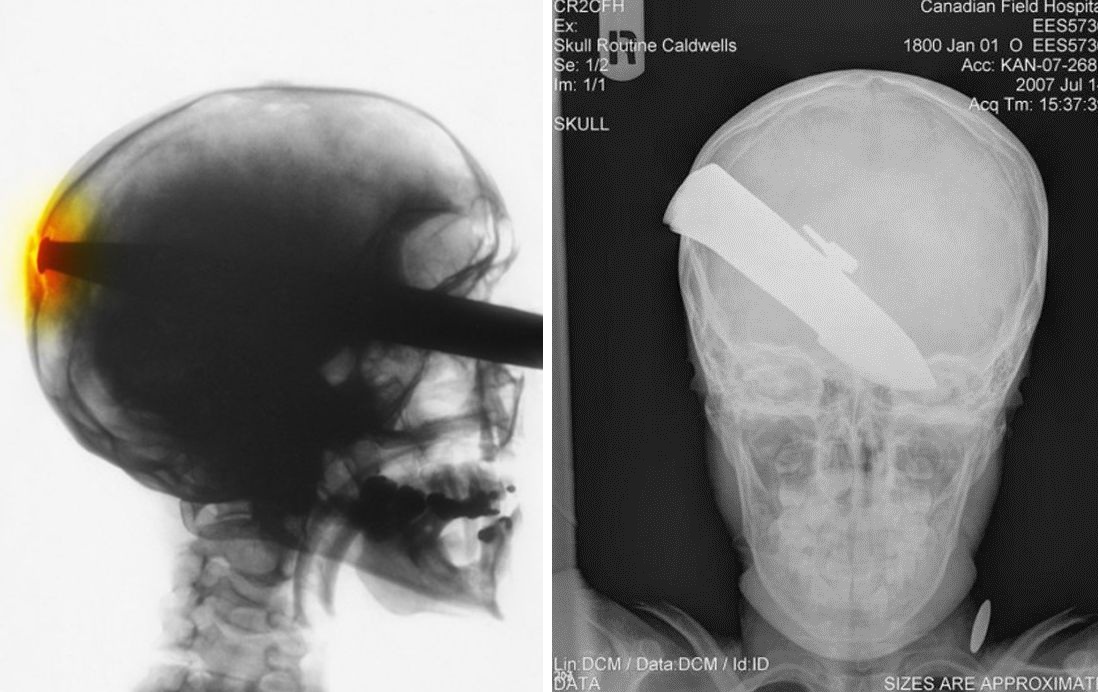

Жуткие рентгеновские снимки

Порой даже не верится, с какими странными и необычными повреждениями в травматологию могут поступить пострадавшие. Всю эпичность профессии врачей травматологии могут с легкостью подтвердить рентгеновские снимки. Просто жесть, да и только..